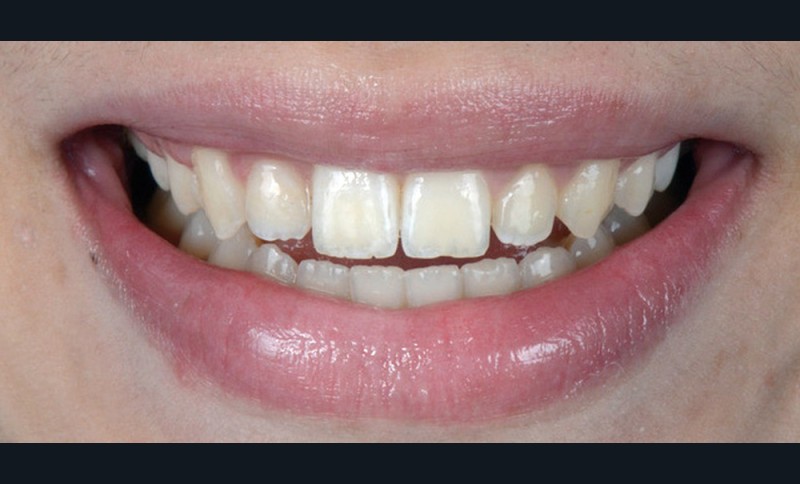

C’est à ces questions que nous permettront de répondre les deux premiers conférenciers, parodontologistes : le Dr Béatrice Straub nous présentera le renfort parodontal minéralisé, technique qu’elle a développée et pratique depuis de nombreuses années, pour éviter les préjudices des mouvements orthodontiques à risque, notamment lors des décompensations préchirurgicales (fig. 1a-d) ; le Pr Anton Sculean abordera le thème des greffes, avec leurs indications, les différentes techniques à privilégier et illustrera ses propos par de nombreux cas cliniques aux résultats esthétiques impressionnants.

Les Drs Marie Clément et Clara Marcoux aborderont ensuite les différents apports de la dentisterie esthétique aux traitements orthodontiques. Les problèmes de dyschromies isolées ou généralisées, congénitales ou acquises seront développés ainsi que les anomalies de proportions dentaires (dents riziformes…), le maquillage (transformation d’une canine en incisive latérale…) et le remplacement des dents antérieures. Les auteurs présenteront l’intérêt du Digital Smile Design dans le diagnostic et la communication et l’arsenal thérapeutique à notre disposition pour améliorer la satisfaction de nos patients (éclaircissement, traitement des taches de l’émail, composites stratifiés, fig. 9a-d).